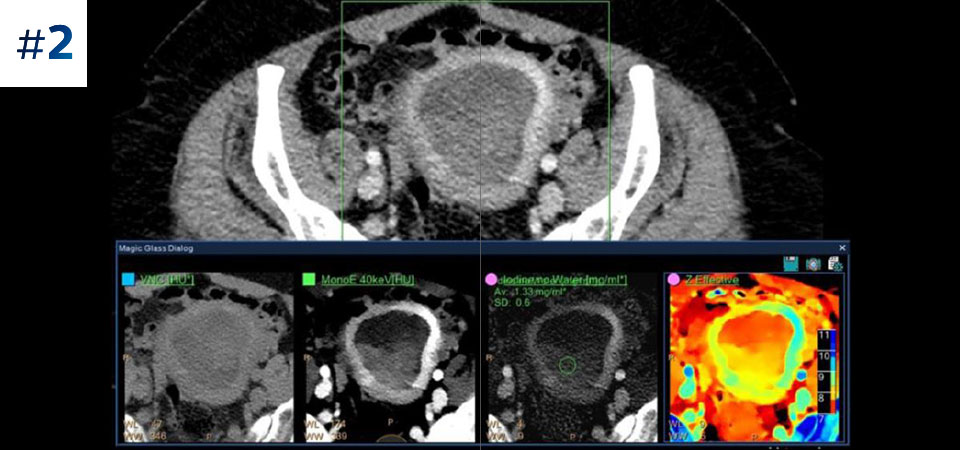

通常どおりにスキャン いつでもどの患者に対しても、1回の高速な低線量スキャンで標準データおよびスペクトラルデータを取得できます。

常に使用可能 スペクトラルデータは常に100%使用可能であり、検査結果はいつでも、オンデマンドだけでなく、レトロスペクティブに取得することもできます。

フォローアップ検査の削減 組織の特性評価と視覚化が改善されることにより、患者の検査が最適でなかった場合や、偶発病変が見つかった場合に、フォローアップスキャンを行う必要性が低減される可能性があります。

さまざまな患者タイプ 小児患者から肥満患者まで、幅広い患者タイプにメリットがあります。